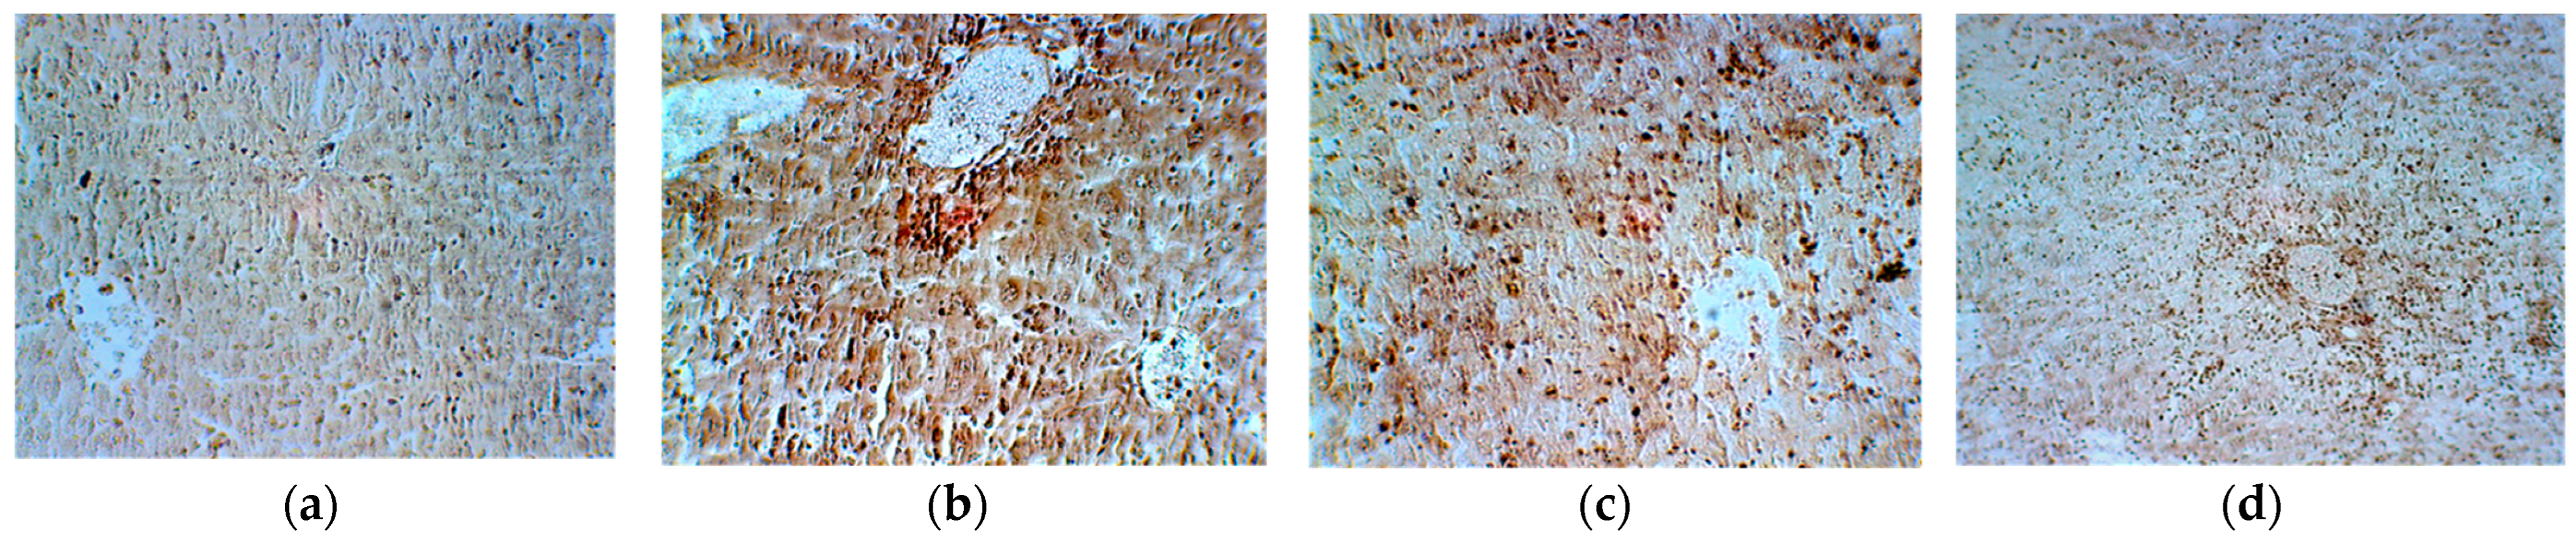

| Group 1 Ascites | Group 2 Ascites + Cyclophosphamide | Group 3 Cyclophosphamide + E. hirsutum Extract | Group 4 E. hirsutum Extract | |

|---|---|---|---|---|

| Reticulin | 0 | 4+ | 2+ | 1+ |

| Van Gieson | 0 | 0 | 3+ | 1+ |